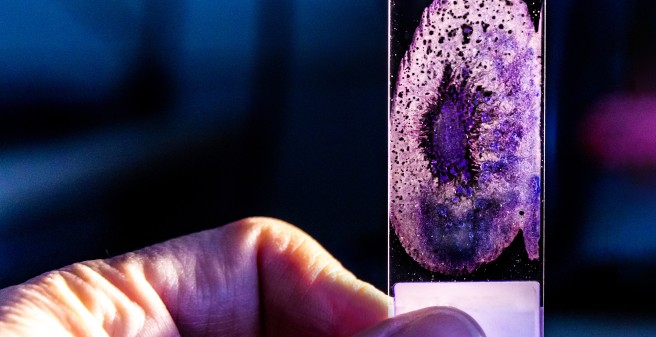

Translational Osteology and Biomechanics & Histologie

The section Translation & Histology is mainly concerned with the comprehensive histological analysis of bone and bone-associated cells. The focus lies on the translation of mechanical to biological signals, the patho-mechanisms of genetic disorders of the musculoskeletal system and the implant/biomaterial interface with bone.